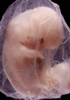

Carnegie Stage 19 (47 post-ovulatory days)

Most embryos at stage 19 are approximately 47-48 post-ovulatory days old and measure 17-20 mm in length. Distinguishing criteria for this stage include straightening of the trunk, the limbs extend nearly directly forward, toe rays are prominent, but interdigital notches have not yet appeared in the foot.

Although some of the photographs below show abnormal embryos, the animations and MRI slice images all depict normal embryos. Abnormal embryos are noted in the titles of the large photos when they are opened.

Photographs